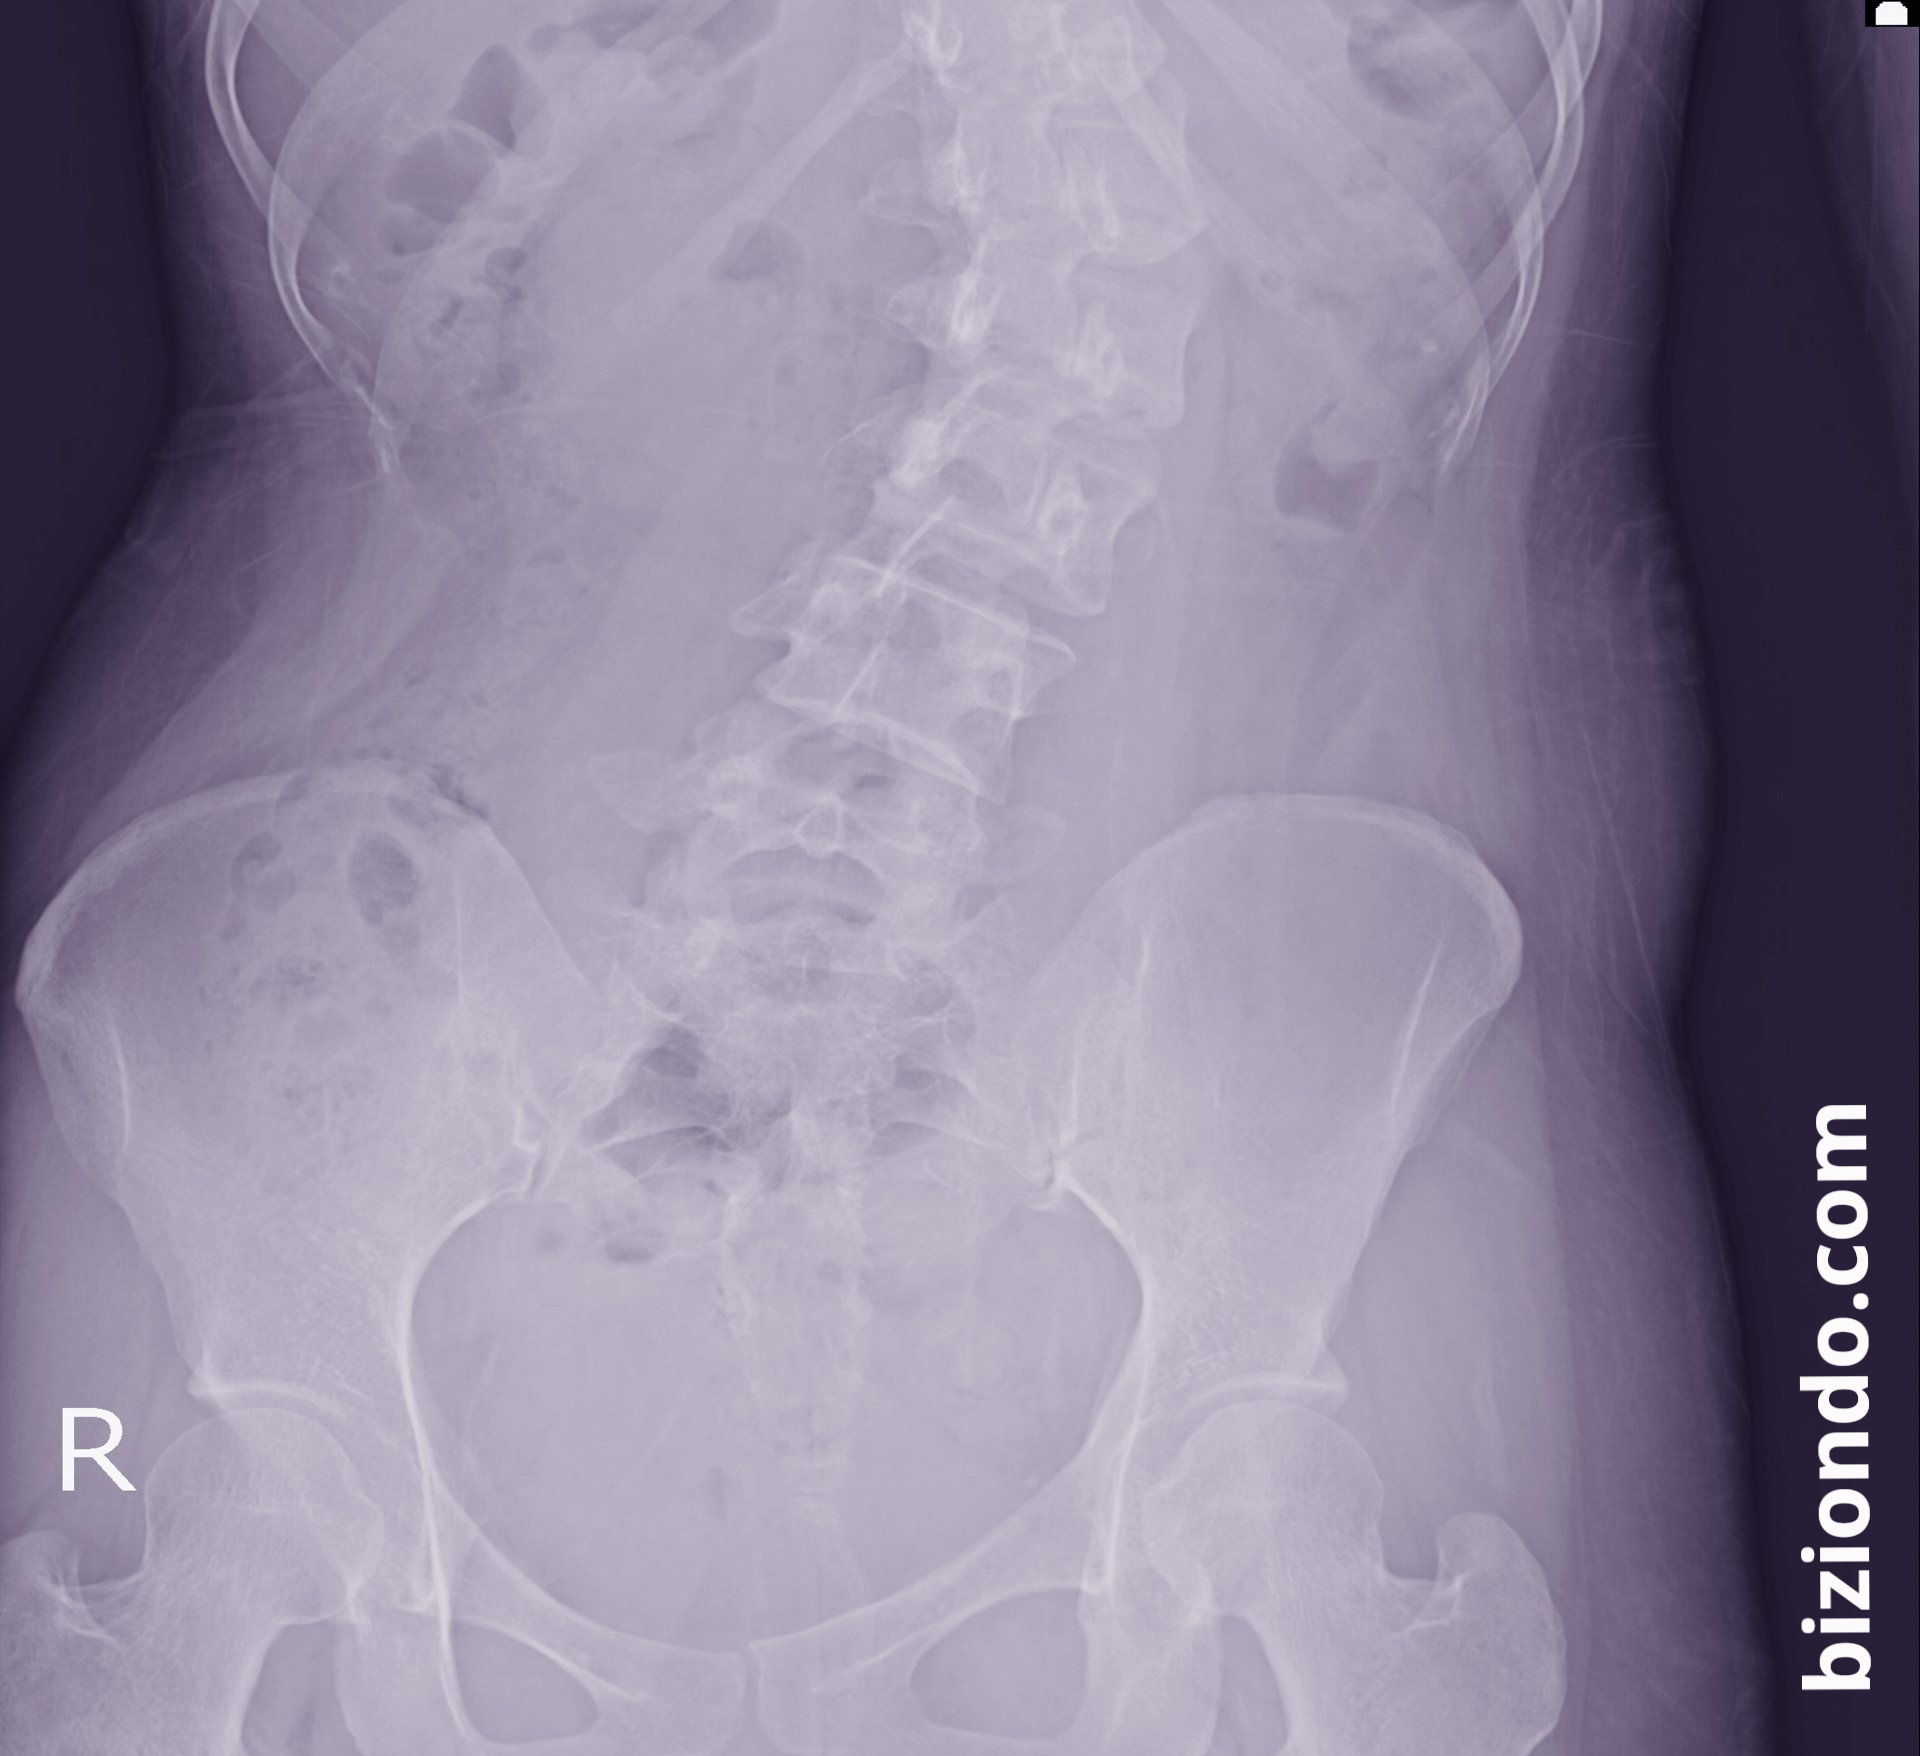

Scoliosis is an abnormal curvature of the spine that can be shaped like an "S" or a "C." Although it's usually diagnosed in childhood or adolescence, it can also occur in adults, especially due to natural wear and tear of the discs.

X-rays and imaging studies

X-rays are the most commonly used method. At Biziondo, we have advanced studies that allow us to accurately measure the curvature angle (Cobb angle) and design a personalized treatment plan.